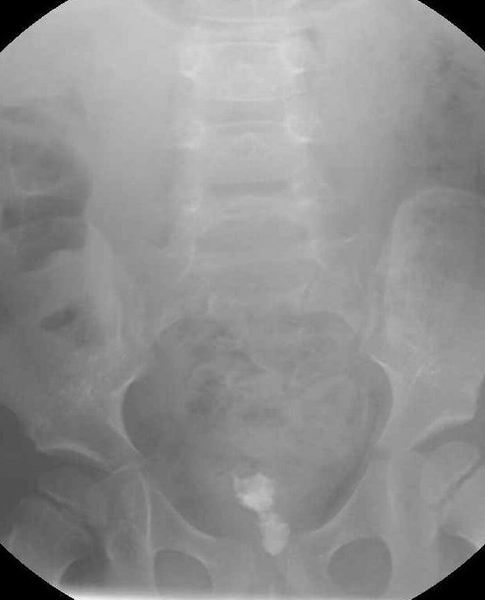

Cystografie